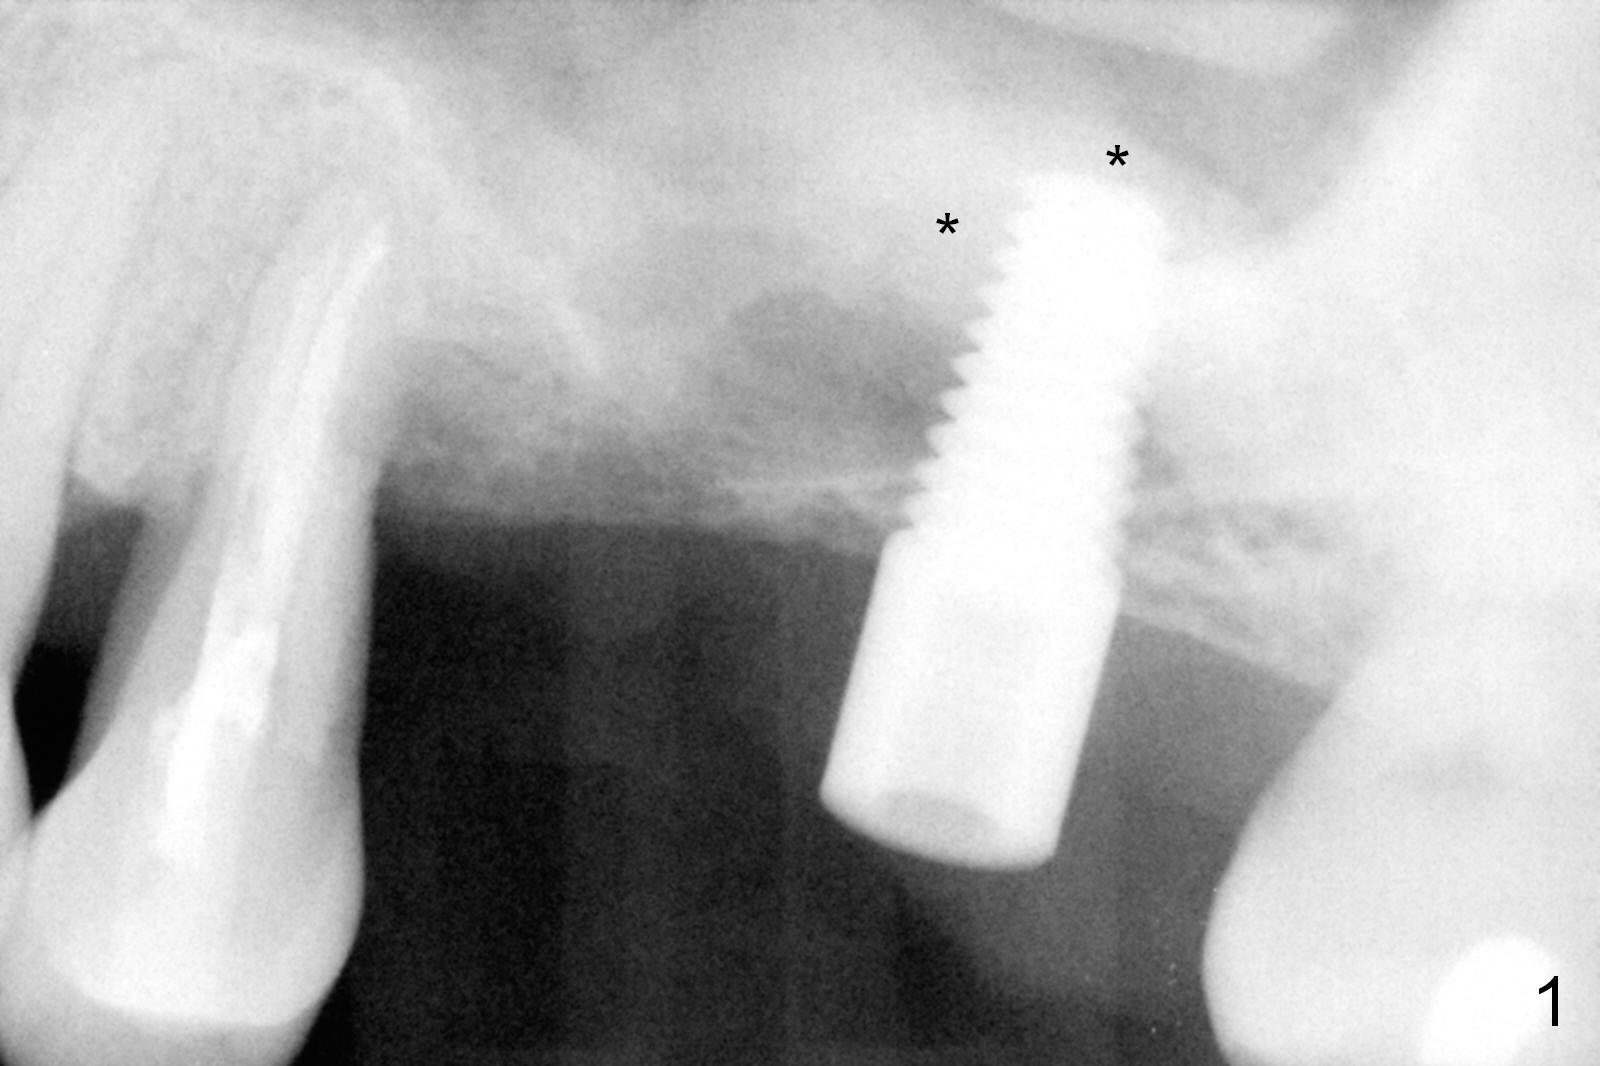

Hemorrhage Associated with Lateral Window

Mild to moderate hemorrhage is encountered as soon as incision is made for the lateral window. It is a concern prior to bone graft and implant placement. Hemorrhage appears to come from the sinus. Bleeding may wash away the graft. Therefore several pieces of Collagen Dressing are inserted into the sinus for hemostasis, followed by placement of Osteogen (Fig.1 *) and implant (5x14 mm, tissue-level). After placement of the 2nd implant, more Osteogen is placed buccal to the implants. Insertion torque is ~ 35 Ncm. Abutments (Fig. 2: 4x5 mm) are placed to hold perio dressing in place (no immediate provisional). In fact, the patient returns within 20 minutes postop because hemorrhage from the incision. Hemostasis is achieved with a few pieces of gauze in the buccal vestibule. Ice pack is recommended. By the evening, the patient reports minimal oozing. When perio dressing is lost 10 days postop, the wound opens (Fig.3). Later the wound heals. It appears that an immediate provisional provides the wound with temporary protection. The abutments without provisional is irritating to the soft tissue (the cheek in this instance). They have to be removed until the implants osteointegrate. PA taken 4 months postop shows the bone in the sinus surrounding the implants (Fig.4 *). The gingiva around the implants looks normal (Fig.5), although there is occasional and mild itching in the skin over the left sinus.